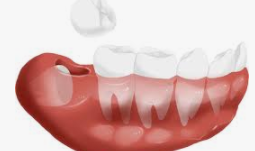

사랑니가 나면서 통증과 붓는 증상이 있다면 일단 해당 부위에 냉찜질로 열을 식혀주시는게 통증 완화에 도움이 됩니다. 하지만 집에서 할수 있는 방법은 더이상 없고 치과를 방문하여 치료를 받으시는게 좋습니다. 만약 사랑니가 자라고 있는데 치료를 하지 않고 방치를 한다면 좁은 턱 사이에 치아들이 서로 비집서 버티기 때문에 치아 배열에 문제가 생길수 있습니다.

그렇기 때문에 사랑니가 자랄경우 치과를 방문하여 발치하는 것이 가장 좋습니다. 발치 후에는 2시간동안 음식은 삼가하고 뜨거운 음식보단 차가운 음식을 먹어 지혈을 먼저하는 것이 좋습니다.